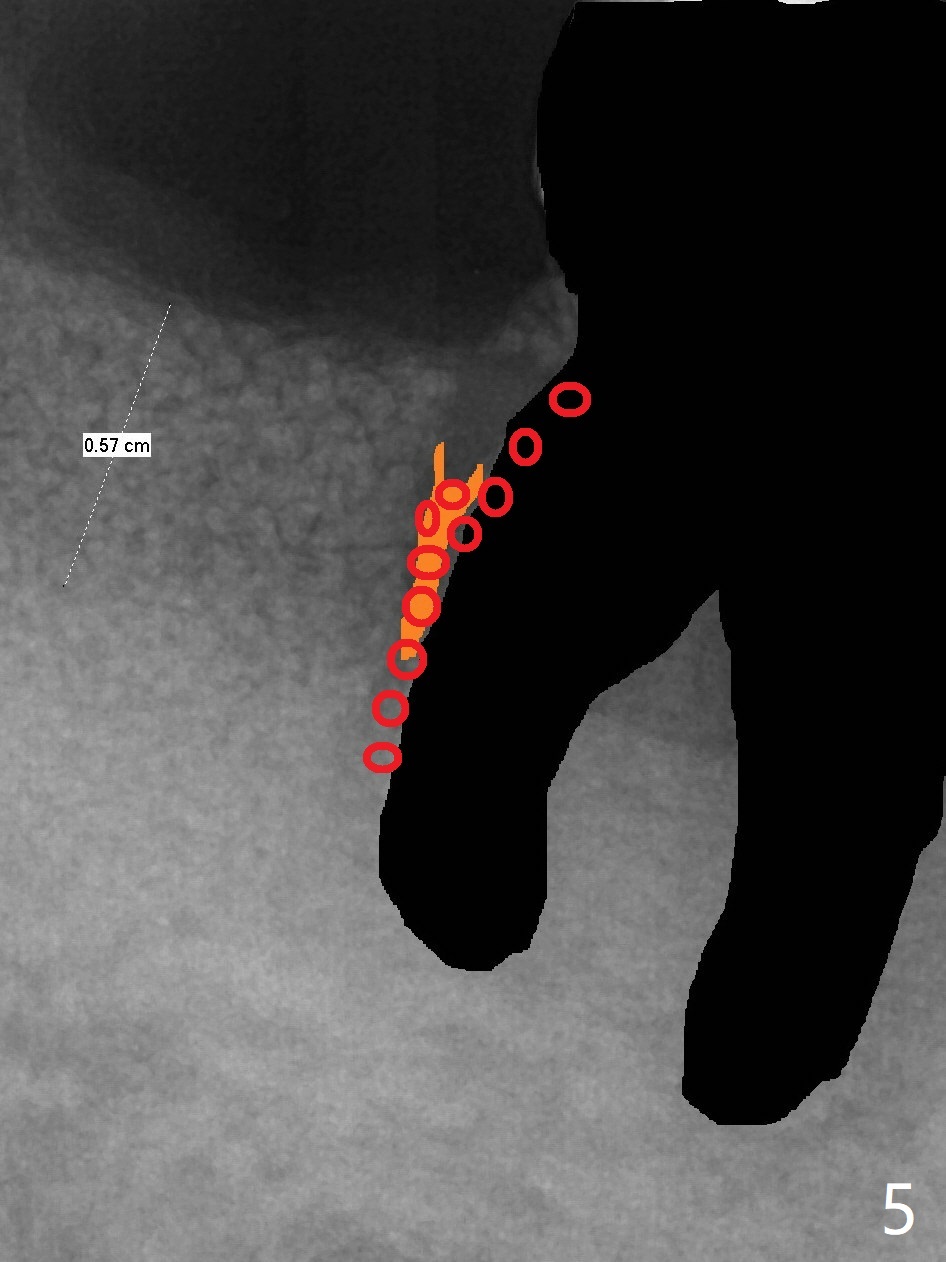

44岁男,吸烟,一天半包,严重牙周病,左上托牙,右下7骨质吸收(图一),松动,影响吃饭,起初他不同意植骨,后来改变主意。拔牙时发现牙龈袋特别深,清创(包括近中)后,放置许多骨粉(皮质),骨高度至少增加5-6毫米(图二)。不可吸收膜,PTFE缝线。如果以后6号牙需要拔除(图三黑色),为了维持龈乳头,牙间牙龈下部分应该切除(图四橘黄色),空间由骨粉充填(图五红色圆圈),以便重新建立牙间牙槽嵴。